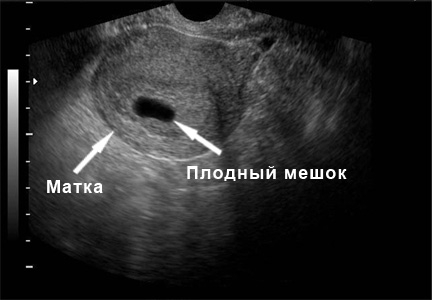

На этом этапе ультразвуковое исследование уже может зафиксировать наличие беременности. Она выглядит как маленький черный кружок, диаметр которого составляет всего несколько миллиметров. Это плодный мешок. На четвертой неделе беременности ультразвуковая диагностика также показывает расширение сосудов матки, что является нормальным явлением.